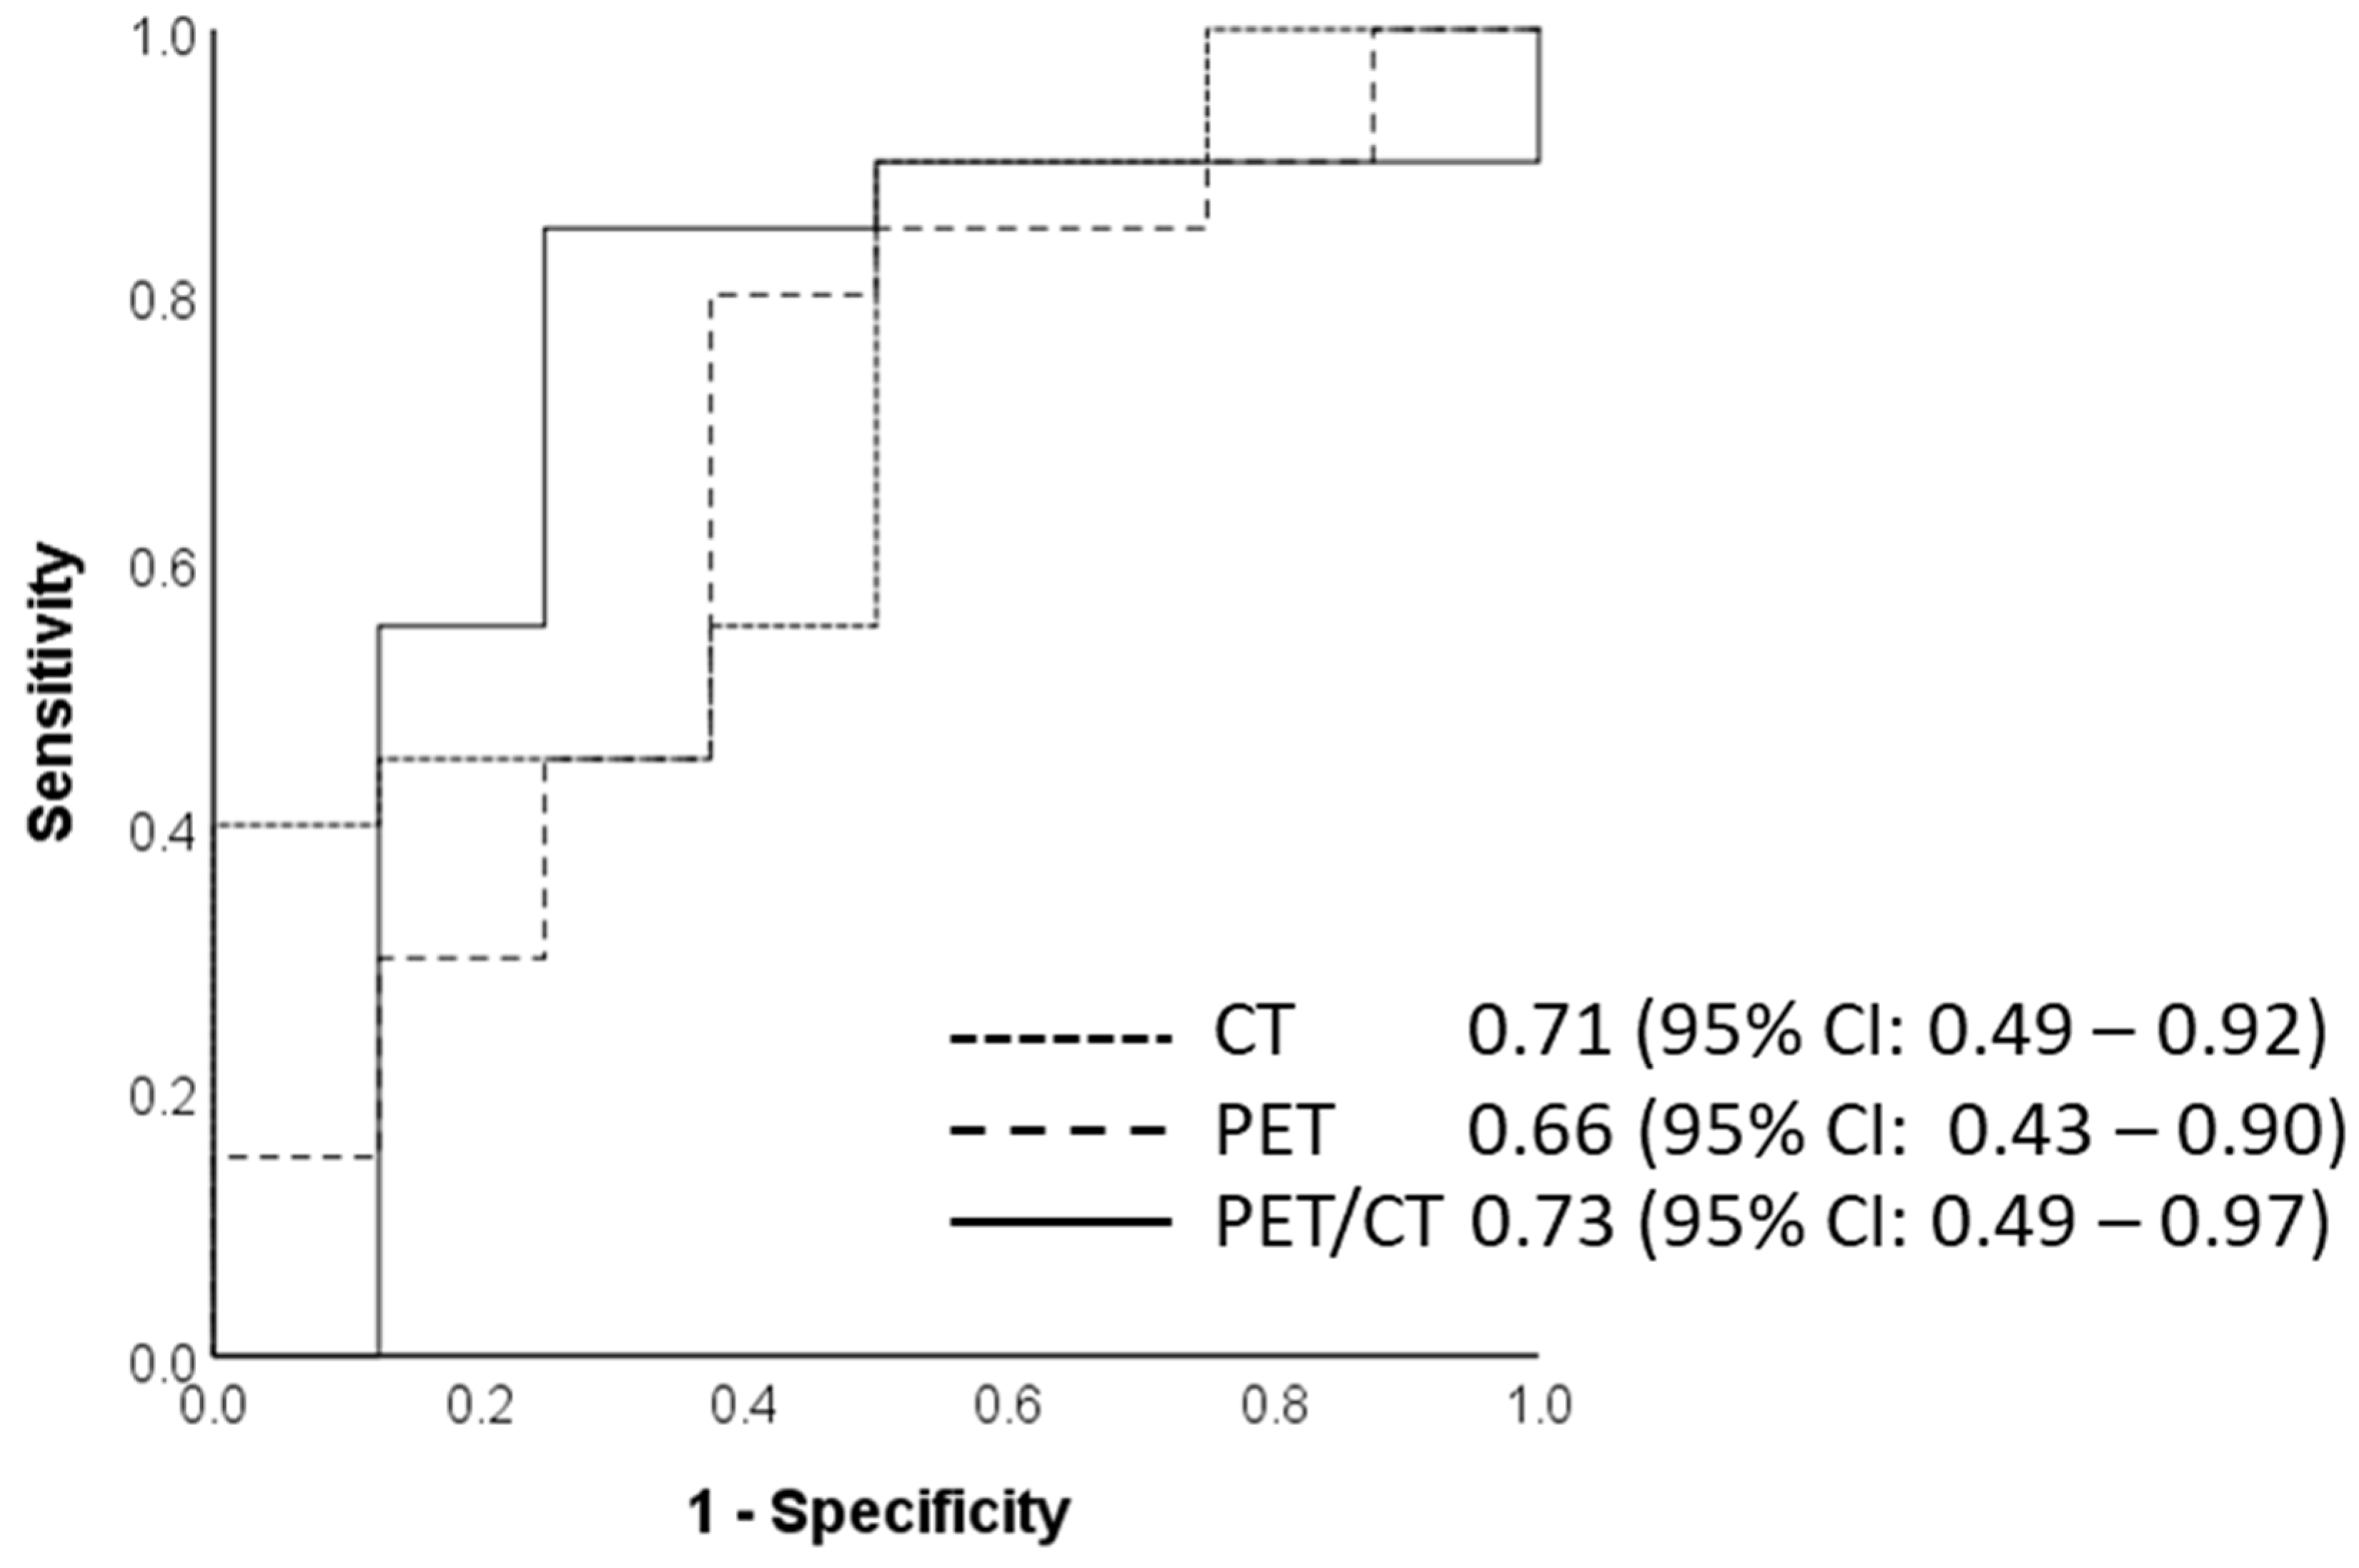

3.2. Diagnostic Accuracy of CT, PET, and Combined PET/CT Training and Test Datasets for Various Clinical Parameters

| Clinical Parameter | Training CT Dataset | Test CT Dataset | Training PET Dataset | Test PET Dataset | Training Combined PET/CT Dataset | Test Combined PET/CT Dataset |

| Nodal Category | 64.3 (51.9–75.4) | 69.0 (49.2–84.7) | 85.7 (75.3–92.9) | 86.2 (68.3–96.1 | 87.1 (77.0–94.0) | 86.2 (68.3–96.1) |

| Tumor Category | 90.3 (81.0–96.0) | 70.4 (49.8–86.3) | 83.3 (72.7–92.1) | 70.4 (49.8–86.3) | 83.3 (72.7–91.1) | 81.5 (61.9–93.7) |

| PET Responders | 69.0 (55.5–80.5) | 60.0 (40.6–77.3) | 72.4 (59.1–83.3) | 66.7 (47.2–82.7) | 75.9 (62.8–86.1) | 70.0 (50.6–85.3) |

| Progression-Free Survival | 66.1 (53.0–77.7) | 60.7 (40.6–78.5) | 77.4 (65.0–87.1) | 75.0 (55.1–89.3) | 77.4 (65.0–87.1) | 75.0 (55.1–89.3) |

| Overall Survival (3 Yrs) | 56.0 (41.3–70.0) | 51.7 (32.6–70.6) | 58.0 (43.2–71.8) | 55.2 (35.7–73.6) | 68.0 (53.3–80.5) | 62.1 (42.3–79.3) |